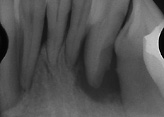

| 初診時口腔内写真・レントゲン写真 |

前歯部では、歯間が離開しており、唇側傾斜がある。全顎的に歯肉の炎症も著明である。レントゲンでは、全顎的に根の1/2程度の骨吸収がある。また一部には垂直性の骨吸収があり、第一大臼歯部は、根尖部まで吸収している部位もある。 |